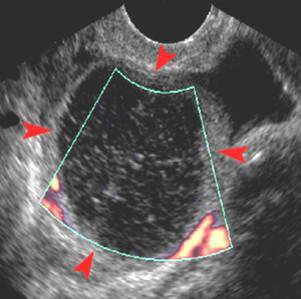

Hepatic Cysts

More commonly in women, thick fluid, cyst can hemorage. Leads to more serious conditions.. infection, absess, necrosis

Hepatic Cysitc Lesion

Liver custs are common, usual Benign

Asymotomatic

Large cyst are at risk for compressing hepatic vasculature and duct syspe,